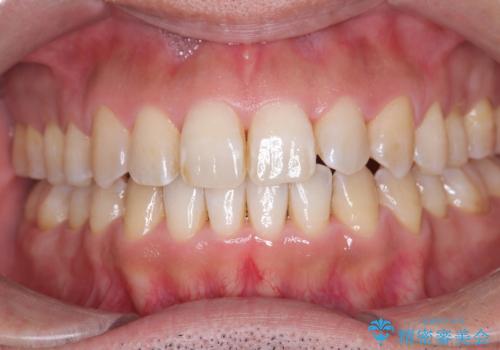

目立たない矯正で八重歯を改善

- 左上の八重歯を気にされて来院されました。精密な検査の結果、歯列全体を広げながら八重歯を奥へ移動させることで、美しい歯並びと機能的な咬み合わせが得られると診断。患者様のご希望に合わせ、透明で目立ちにくい**インビザライン(マウスピース矯正)**による治療計画を立案しました。抜歯を避け、歯を少しずつ遠心(奥)へ移動させることで、歯が並ぶスペースを確保し、叢生(歯のデコボコ)を改善します。

今回の矯正治療では、透明なマウスピース型の装置インビザラインを使用しました。この装置は目立ちにくく、取り外しが可能なため、食事や歯磨きも普段通りに行えます。遠心移動という方法で奥歯を後方に動かし、前歯を並べるためのスペースを確保。これにより、抜歯することなく、左上の八重歯を含む叢生を効果的に改善し、整った美しい歯並びと良好な咬み合わせを獲得していただけました。